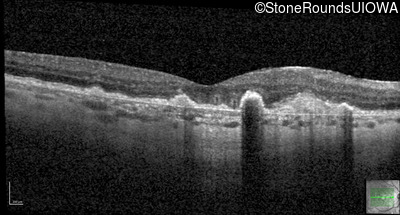

Malattia Leventinese (IIJ)

Malattia Leventinese (IIJ)

This 43 year old woman has experienced a gradual reduction in her central vision for the past 3 years.

| Malattia Leventinese | EFEMP1 | Arg345Trp CGG>TGG | AD |